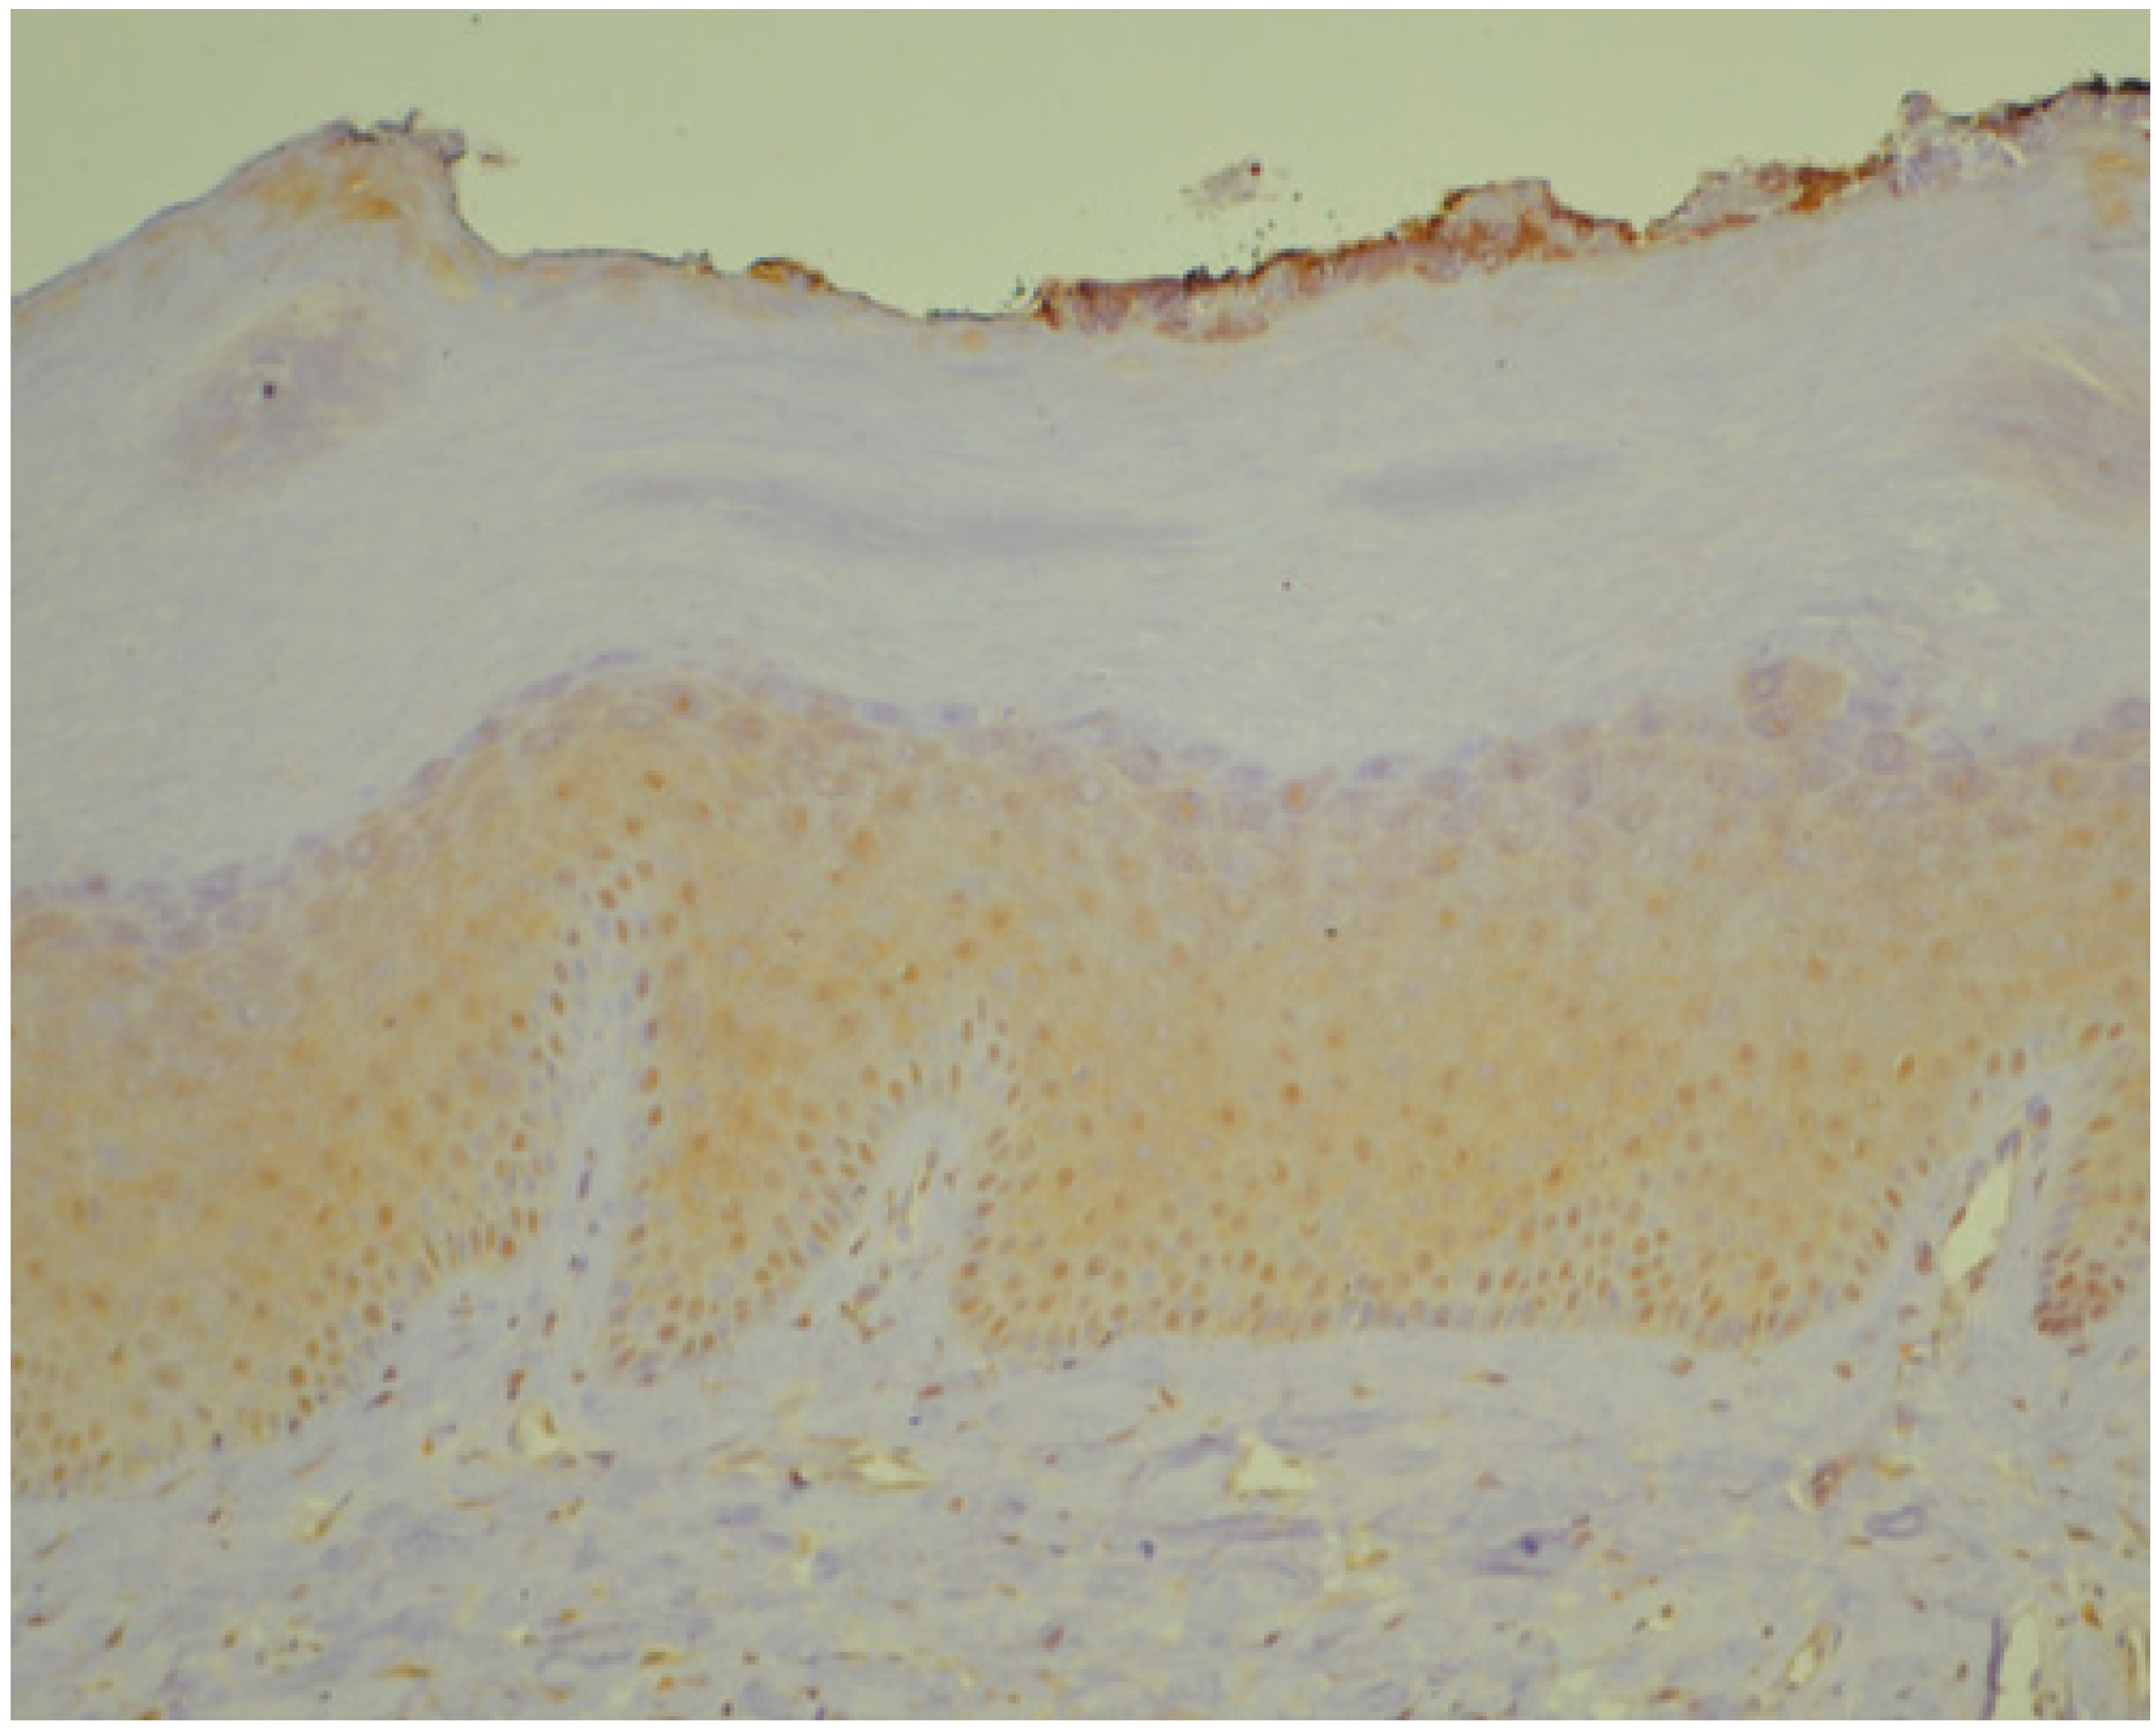

3.1. Histopathology and Immunohistochemistry